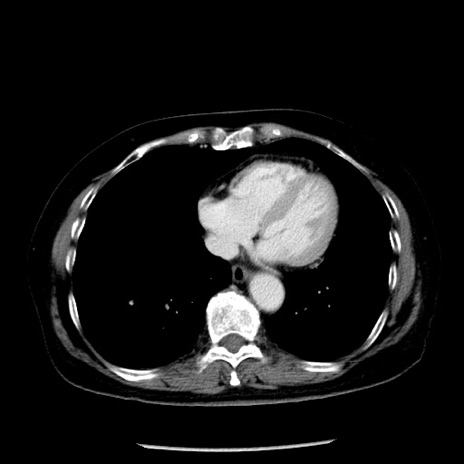

症例13(横断像)

【症例】70歳代女性

【主訴】腹痛、嘔吐

【現病歴】15時間程前(昨晩)より腹痛あり。今朝になっても症状の改善なく、嘔吐あり。腹痛も増悪あり、救急外来受診。

【既往歴】子宮癌全摘術後

【身体所見】意識清明、BP 121/72mmHg、P 74bpm、SpO2 100%(RA)、腹部:平坦・軟、腸雑音ほぼ聴取せず。下腹部・心窩部・臍左上に圧痛あり。反跳痛なし。

【データ】WBC 10600、CRP 0.15